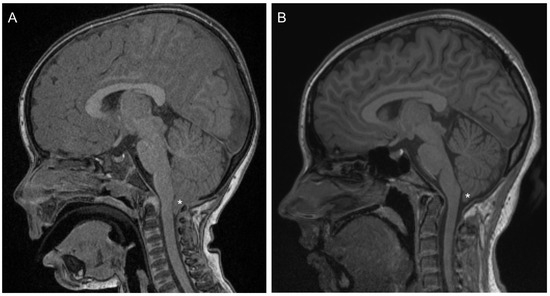

This case report provides findings for a 17-year-old female (Patient 1) with a history of Chiari 1 malformation and symptoms of cerebellar abnormality. She was diagnosed at age 3 years following extended periods of nausea, vomiting and headache, absence seizures and developmental delays affecting both physical and speech/communication milestones. Structural magnetic resonance imaging revealed a 12 mm herniation of the cerebellar tonsils and associated compression of the cervico-medullary junction (Figure 1A). Posterior fossa and brainstem structures were otherwise normal, as was the spinal column. At age 3 years 2 months, posterior fossa decompression surgery (occipital craniectomy including the foramen magnum and the arch of C1) was undertaken. Post-operative MRI showed only minor herniation and extension of the tonsillar tip 3.7 mm beyond the foramen magnum. Recent MR imaging, conducted on the same day as auditory testing, showed herniation of the tonsillar tip 6.3 mm below the foramen magnum (Figure 1B).

Figure 1. (A) Pre-operative T1-weighted sagittal MRI showing extent of herniation of the cerebellar tonsils (*) and associated compression of the cervico-medullary junction. (B) T1-weighted sagittal MRI collected 14 years after decompression surgery. The cerebellar tonsils (*) remain herniated by ~6.3 mm.